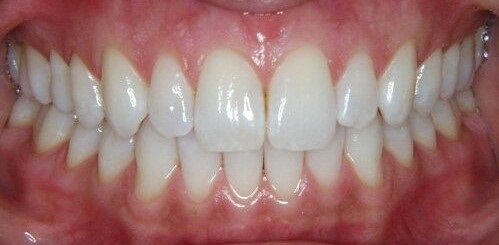

GUM TREATMENTS

Periodontal Plastic Surgery Procedures

Periodontists are often considered the plastic surgeons of dentistry. If you are looking to improve your smile, a periodontist may be able to help.